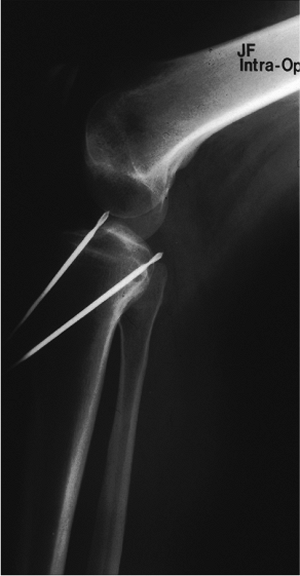

insertion site (Fig. 25.3). A Kirschner (K)

wire is passed with a starting point approximately 3 to 4 cm distal to

the joint line, and an intraoperative fluoroscopy image is obtained.

This K wire is left in place and attention is turned to the ACL tunnel.

The ACL guide is set to 45 degrees and inserted through the

anteromedial portal. A 3/32-inch guide wire is inserted into the center

of the ACL footprint. A fluoroscopic image with the knee in full

extension is now obtained to assess the placement of the K wires. The

ACL wire should be just posterior to Blumenstaat’s line on the lateral,

and the PCL wire should be 2 to 3 cm distal to the ACL wire (Fig. 25.4).

Figure 25.4. Radiographic confirmation of the ACL and PCL tibia-guide wire placement.